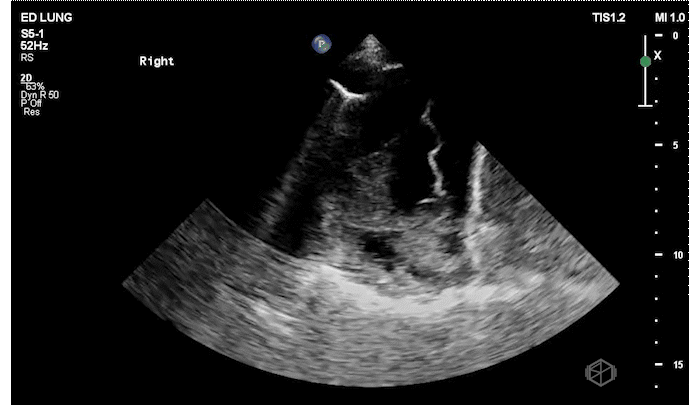

Before even the chest x-ray Dr. Mehta did a lung ultrasound (LUS) that demonstrated the following:

The patient has focal B-lines on the right side with diminished lung sliding. The presence of B-lines rules out pneumothorax. The right lung base has at least a moderate sized complex pleural effusion with septations.

Diagnosis: Complex pleural effusion, empyema